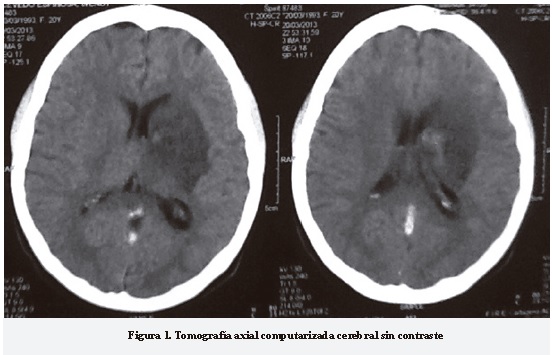

Tomografía axial computarizada de cráneo sin contraste de ingreso, evidencia imagen hipodensa en región paratalámica izquierda con hiperdensidad que sugiere presencia de hemorragia versus neuroinfección (Figura 1).